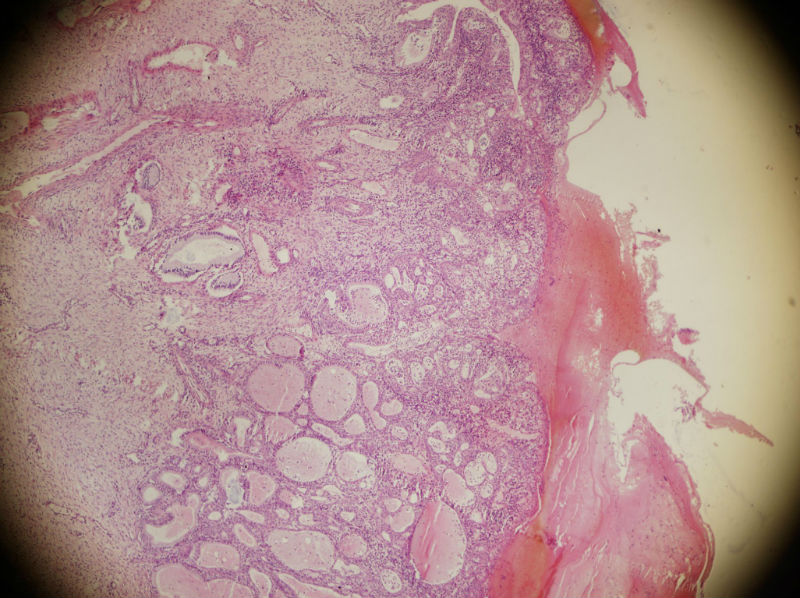

45岁,宫颈息肉?请老师指教

图2